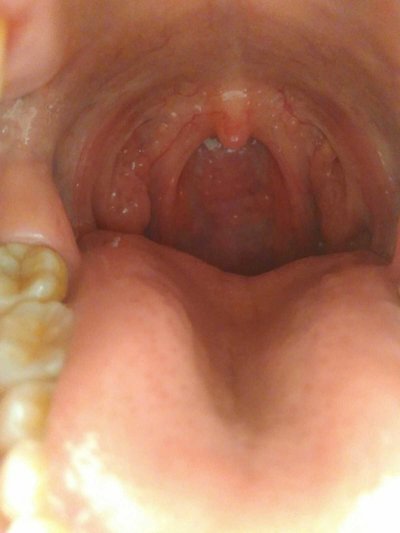

In daily life, if you don't pay attention to hygiene, or poor diet and sleep, it may lead to some diseases. Rotten tongue is a very common oral disease. Rotten tongue has a great influence on diet. How to treat rotten tongue? Let's talk about it

How is tongue root rotten treated?